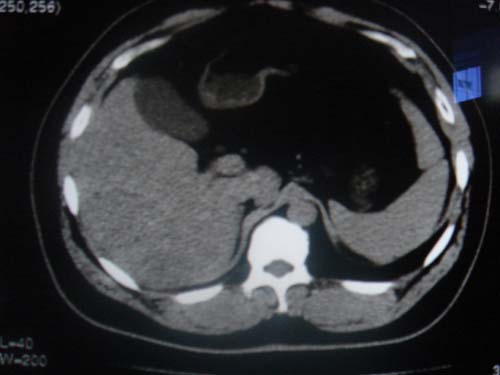

患者 男 40 右上腹不适 有胆囊息肉病史2年

本例就是胆囊比较大,内密度不很均匀,疑有砂砾状结石,未见息肉以及其他异常。

肝脏增大,

最后二副图像示胆囊壁增厚,与肝分界欠清,建议强化ct或磁共振

片中示肝脏的ct值低于脾脏,肝脏右叶外缘部份凹凸不平,考虑脂肪肝,肝硬化可能。结合其检查如b超或ct增强检查。

胆囊未见明显异常,肝脏密度似比脾脏密度低,测量一下ct值排除一下脂肪肝.当然做一下增强或mr就更好了.

肝右叶密度不均,脾大。强烈要求增强扫描除外浸润型肝癌。

肝大   密度降低  脾大  脂肪肝?